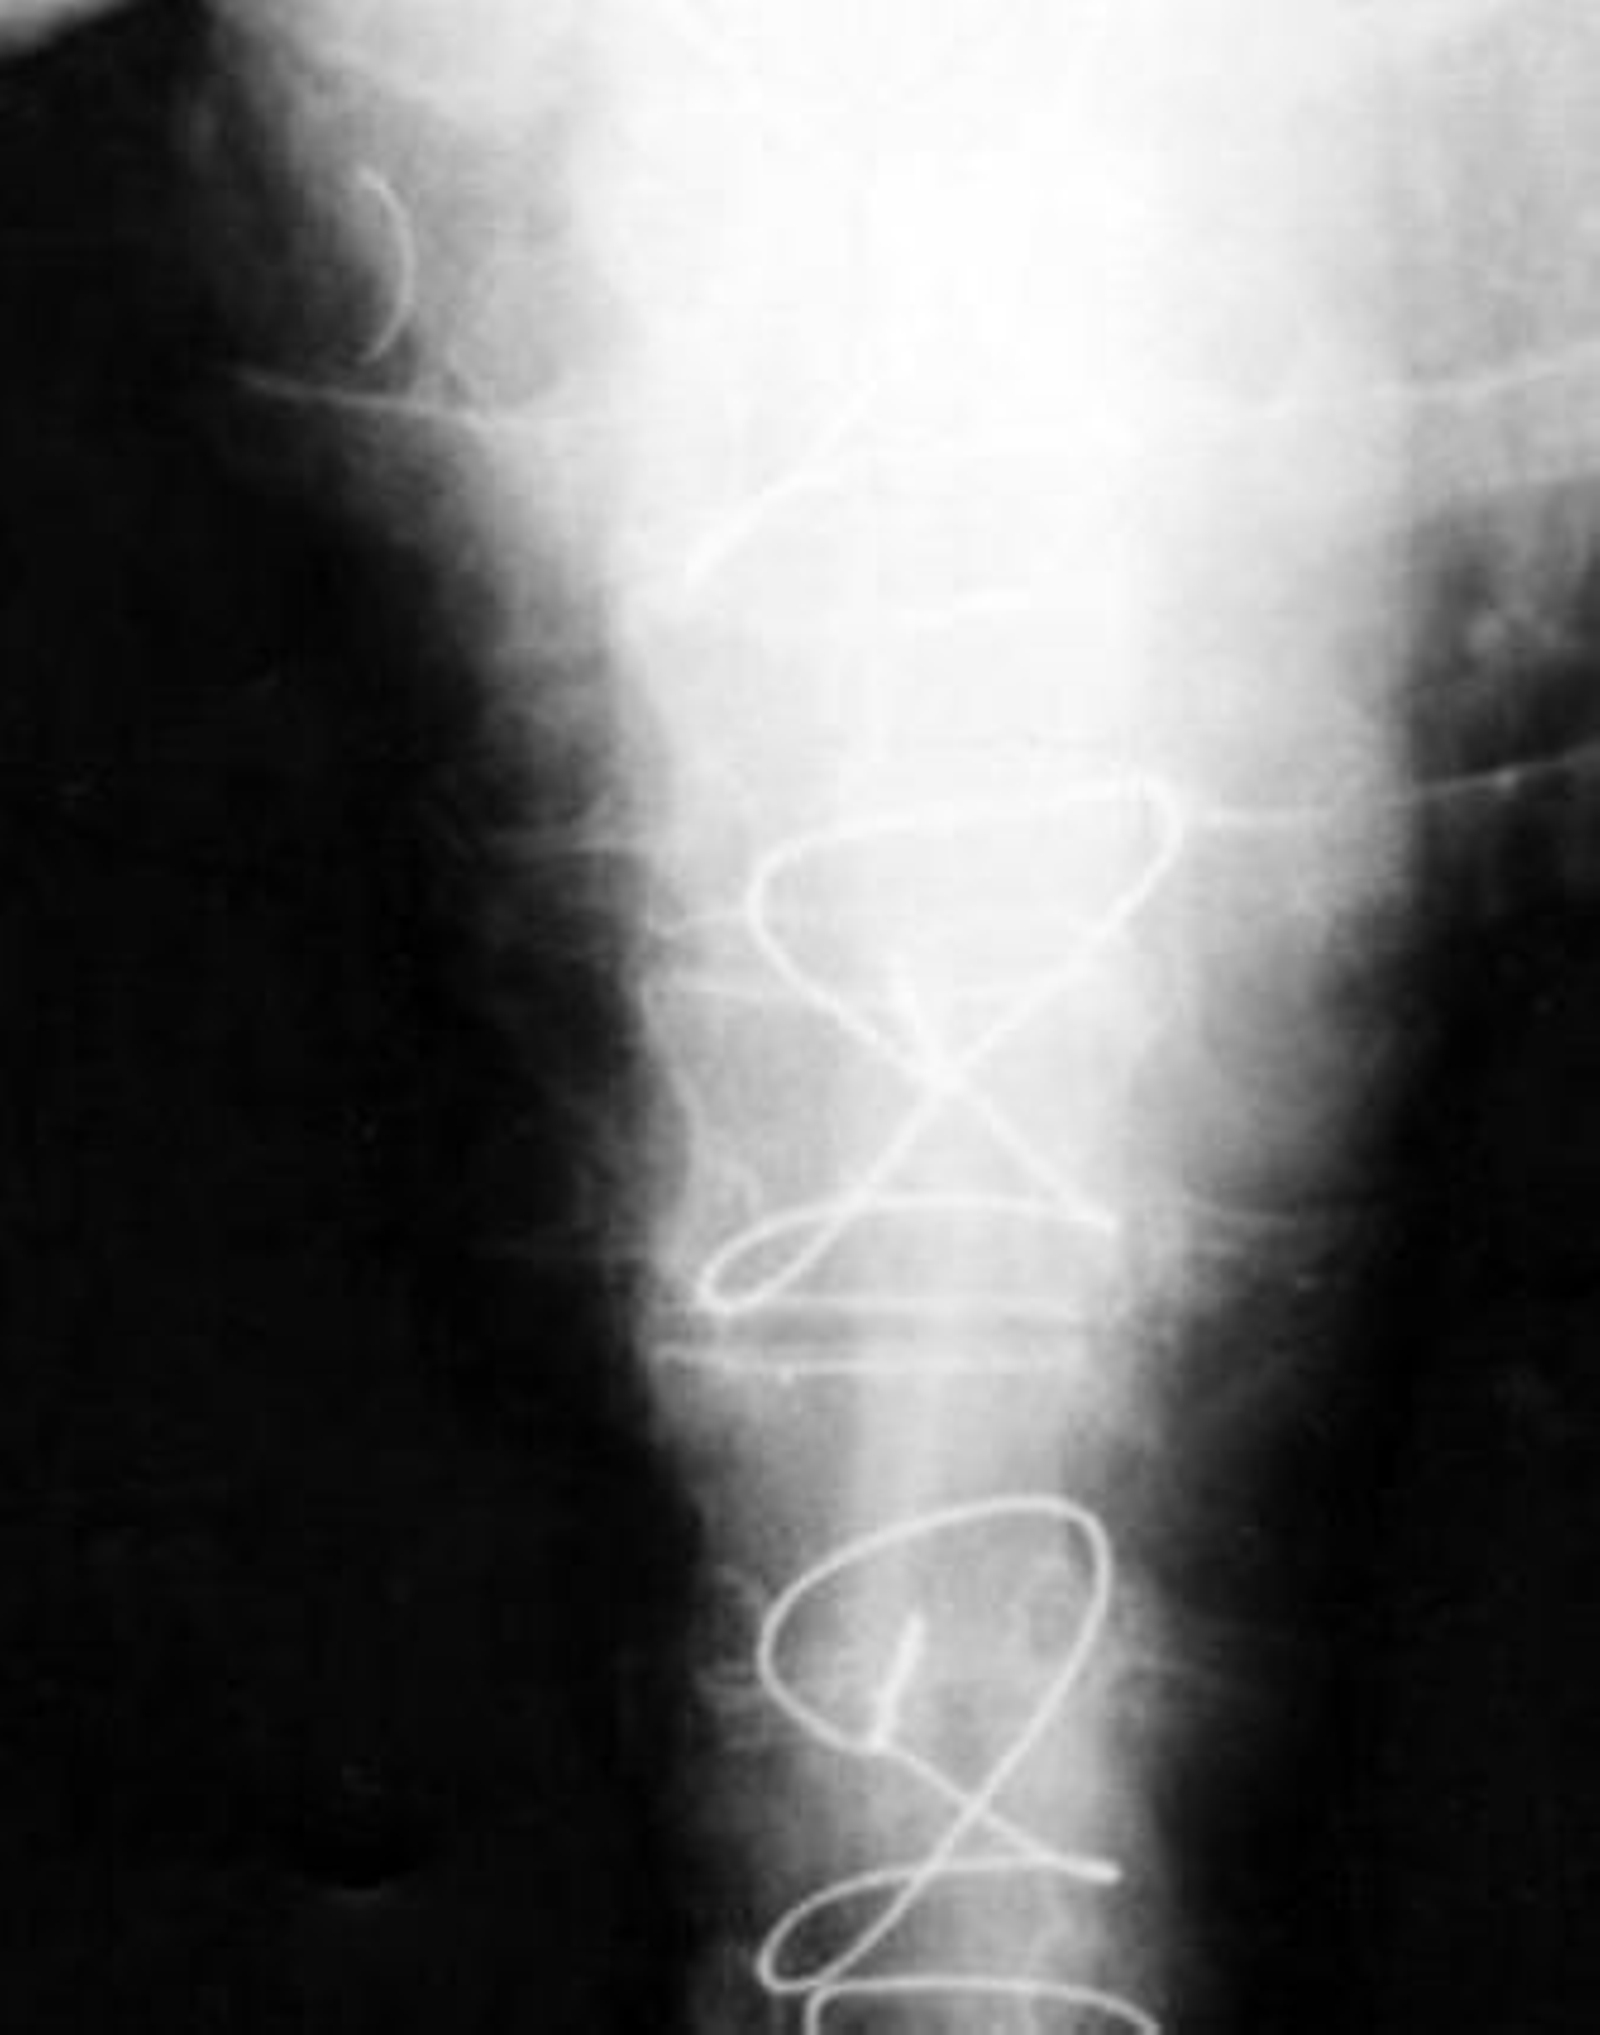

1. Imagen de las pruebas radiológicas realizadas a la paciente en las que se observa (en la ampliación) el cuerpo curvilíneo que resultó ser una aguja de sutura olvidada por el personal médico que le practicó la operación, en la que se intentó reparar el mal funcionamiento de la válvula mitral. Según los expertos, los objetos extraños son englobados por el organismo pero no se descarta que se mueva y tenga consecuencias.

Tras una primera revisión en abril de 2004, en la que no se vio nada raro, la paciente, aún con dolores y malestar, acudió en mayo a Urgencias del Hospital de la Axarquía -en Málaga-, donde, con dolor torácico punzante, le realizan pruebas radiológicas en las que se "evidencia imagen curvilínea de densidad metálica en localización de aurículo derecha". La aguja de sutura.